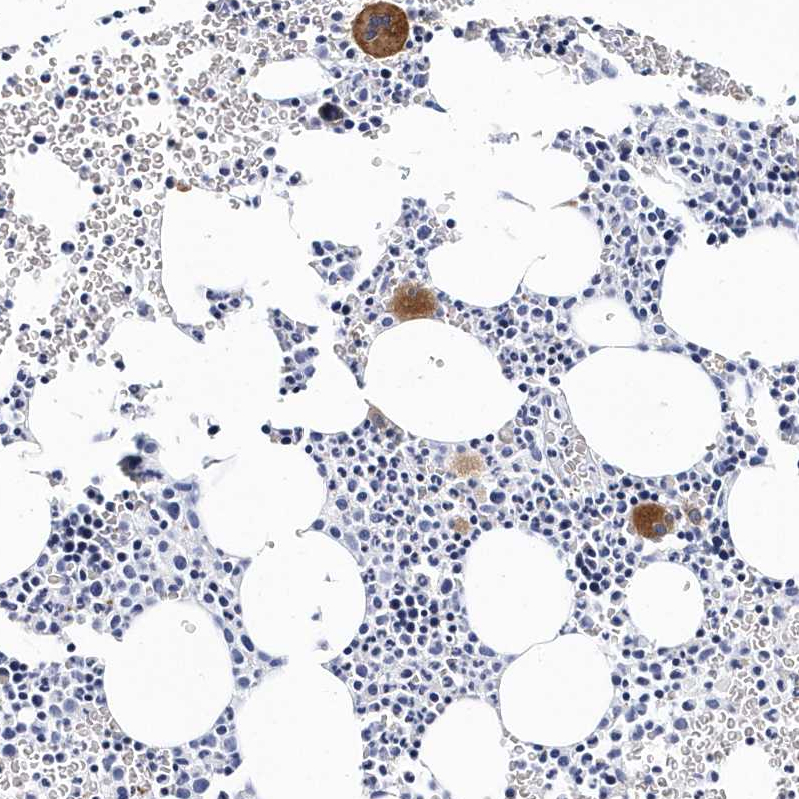

Immunohistochemistry analysis in human bone marrow and tonsil tissues using HPA031170 antibody. Corresponding ITGA2B RNA-seq data are presented for the same tissues.